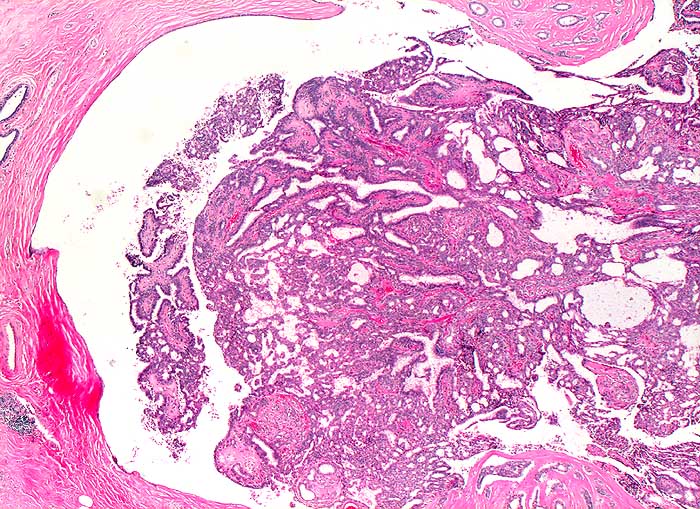

PathoPic ID 5689 - Milchgangspapillom

Milchgangspapillom

benigner Tumor

Mamma

Tubulopapillärer Tumor in einem ausgeweiteten Milchang.

Tastbefund rechts bei 12h, perimamillär mit benignen Schallkriterien. DD: Fibroadenom, Lipom, Fettgewebsnekrose.

Histologie

25